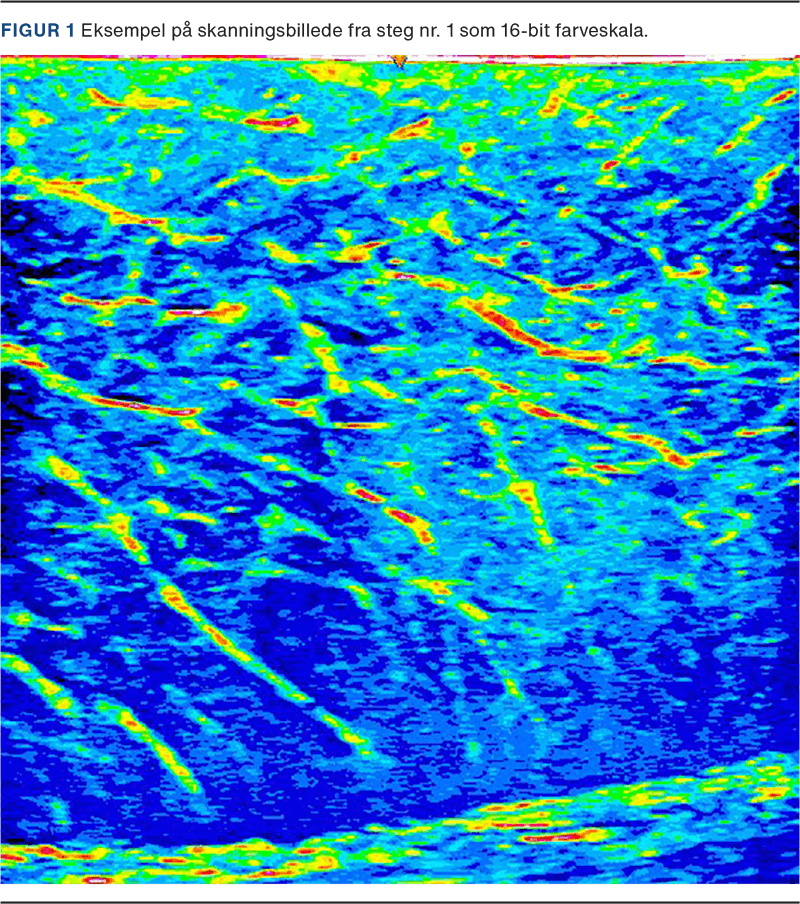

Alle UL-billeder blev gemt på en harddisk og efterfølgende behandlet i R med pakken »EBImage«. Her blev billederne dikotomiseret ud fra værdier fra tidligere studier med en gråskala 48-128. Dette skulle svare til væskeholdigt interstitiel væske. Antallet af pixels i dette interval blev summeret og divideret med total antal pixels. Dette udgjorde procentdelen af væskeholdigt kød.

Efter UL-skanning af stegene havde steg nr. 1 64,26% væskeholdigt kød, steg nr. 2 havde 58,15% væskeholdigt kød, og steg nr. 3 havde 60,33% væskeholdigt kød. Ved steg nr. 3 var begge skanninger i yderste inddeling væsentligt forskellige fra de andre, og ved inspektion af skanningsbillederne var der artefakter på begge billeder. Derfor blev disse billeder fjernet fra analysen, og andelen af væskeholdigt kød blev beregnet. Eksempel på skanningsbillede i 16-bit farveskala ses i Figur 1.